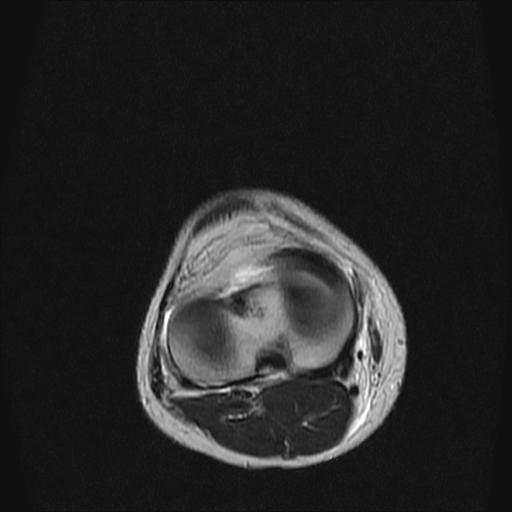

40岁男性,右膝关节外伤,x光平片示,髁间隆突撕脱骨折。

3、关节腔积液。

半月板1-2级损伤   前交叉韧带撕裂伤   关节腔少量积液  诸骨未见新鲜外伤性改变

半月板1-2级损伤   前交叉韧带撕裂伤   关节腔少量积液

3、滑膜炎伴关节腔积液。

3、关节腔积液。4、髁间脊撕脱骨折。